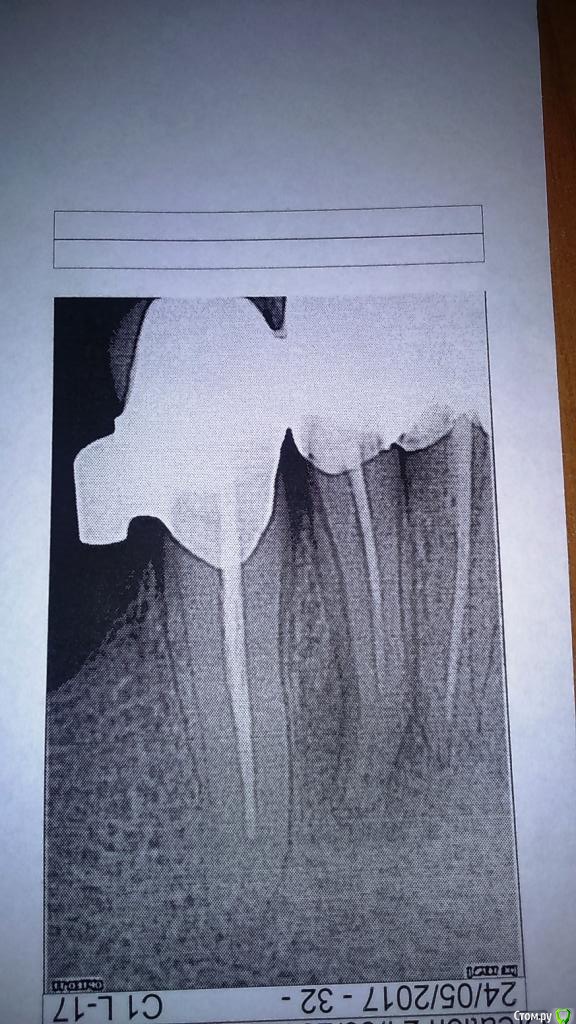

Наина 1973 Опубликовано 24 мая, 2017 Поделиться Опубликовано 24 мая, 2017 Ситуация такова: ничего не болело, образовался свищ, обратилась в клинику - предложили три варианта: удаление зуба, снять коронки и пролечить зуб, сделать ретроградное пломбирование.Снимок на тот момент не дали на руки.Пока я думала и работала врач уехал.Обратилась к другому хирургу, он снимок сделал, сказал что все плохо, все зубы не до пломбированы (лечение в этой же клиники проходила, в карте терапевта есть снимки год назад там было все нормально при установке коронок).Ретроградное пломбирование в этом случае они не делают и в данном случае только резекция верхушки, положить лекарство (не помню как назвали) и жить и надеяться на то что больше они может не воспаляться.Обошла четыре клиники в нашем городе, все говорят про резекцию, в двух вообще сказали, что только снятие коронок.Выехать в другой город для лечения не вариант, я живу в Магадане проезд туда-обратно (без разницы Москва или Хабаровск) сейчас порядка 40-50 тыс.Снять коронки пока не могу, так как там бюгель и сделать конструкцию новую очень дорогоСнимок прикрепляю, он на бумаге, поэтому фотала под разным освещением на всякий случай.Вопрос:- делать или нет резекцию или ходить так дальше и ждать отпуска что бы обратиться в стоматологию в другом городе?- если будет только резекция, вероятность рецидива очень большая? и в случае рецидива только удаление зуба?Спасибо Ссылка на комментарий

Fibez Опубликовано 24 мая, 2017 Поделиться Опубликовано 24 мая, 2017 1. резекцию без ретроградного пломбирования не делать2. если снимать коронки не хочется (+там замковый бюгель? это повлечет за собой и его переделку), то искать терапевта, который возьмется сделать эндо через коронку.3.вероятность рецидива большая4.не обязательно, просто при обострении у Вас будет меньше времени выбирать Ссылка на комментарий

DmitrySH Опубликовано 24 мая, 2017 Поделиться Опубликовано 24 мая, 2017 Через коронку ничего сложного, но нижние резцы имеют такое стоение, что от коронки мало что останется. Вся керамика поколется скорее всего. 3 Ссылка на комментарий